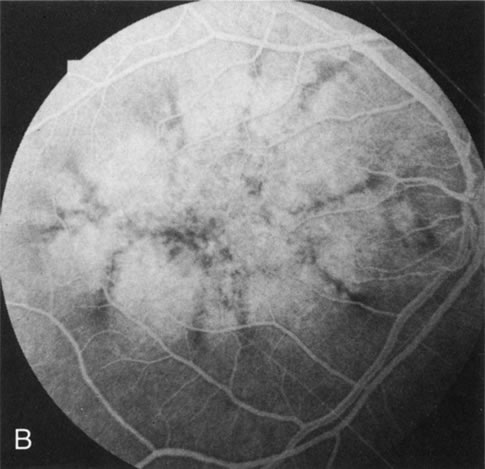

Dye leakage in RP may occur from the retinal vessels or at the level of the retinal pigment epithelium (Fig. 1B).2–4 The leakage may be seen in the macula and posterior pole, along the vascular arcades in the distribution of the radial peripapillary capillaries, and in the periphery (where an exudative vasculopathy resembling Coats' disease is suggested).